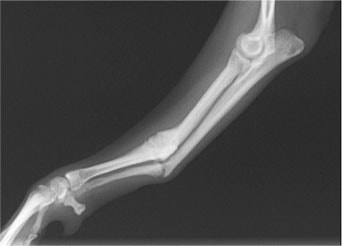

トイプードル 右遠位橈尺骨短斜骨折のALPSによる内固定

Locking Compression Plate

LCPは、スクリュー(ネジ)とプレート(金属の板)をロックする特殊な構造により骨折部位を固定する新しい世代のプレートシステムです。ひとつのホールでロッキングスクリューとスタンダードスクリューの使用を選択できるユニークな構造をしているため、骨折断端間の圧迫を目的とした従来型プレート固定法に加え、高い角度安定性を有するロッキングスクリューを用いた固定法の選択が可能です。従来のプレートシステムでは困難だった部分の骨折や癒合不全の症例に高い治療効果をもたらします。